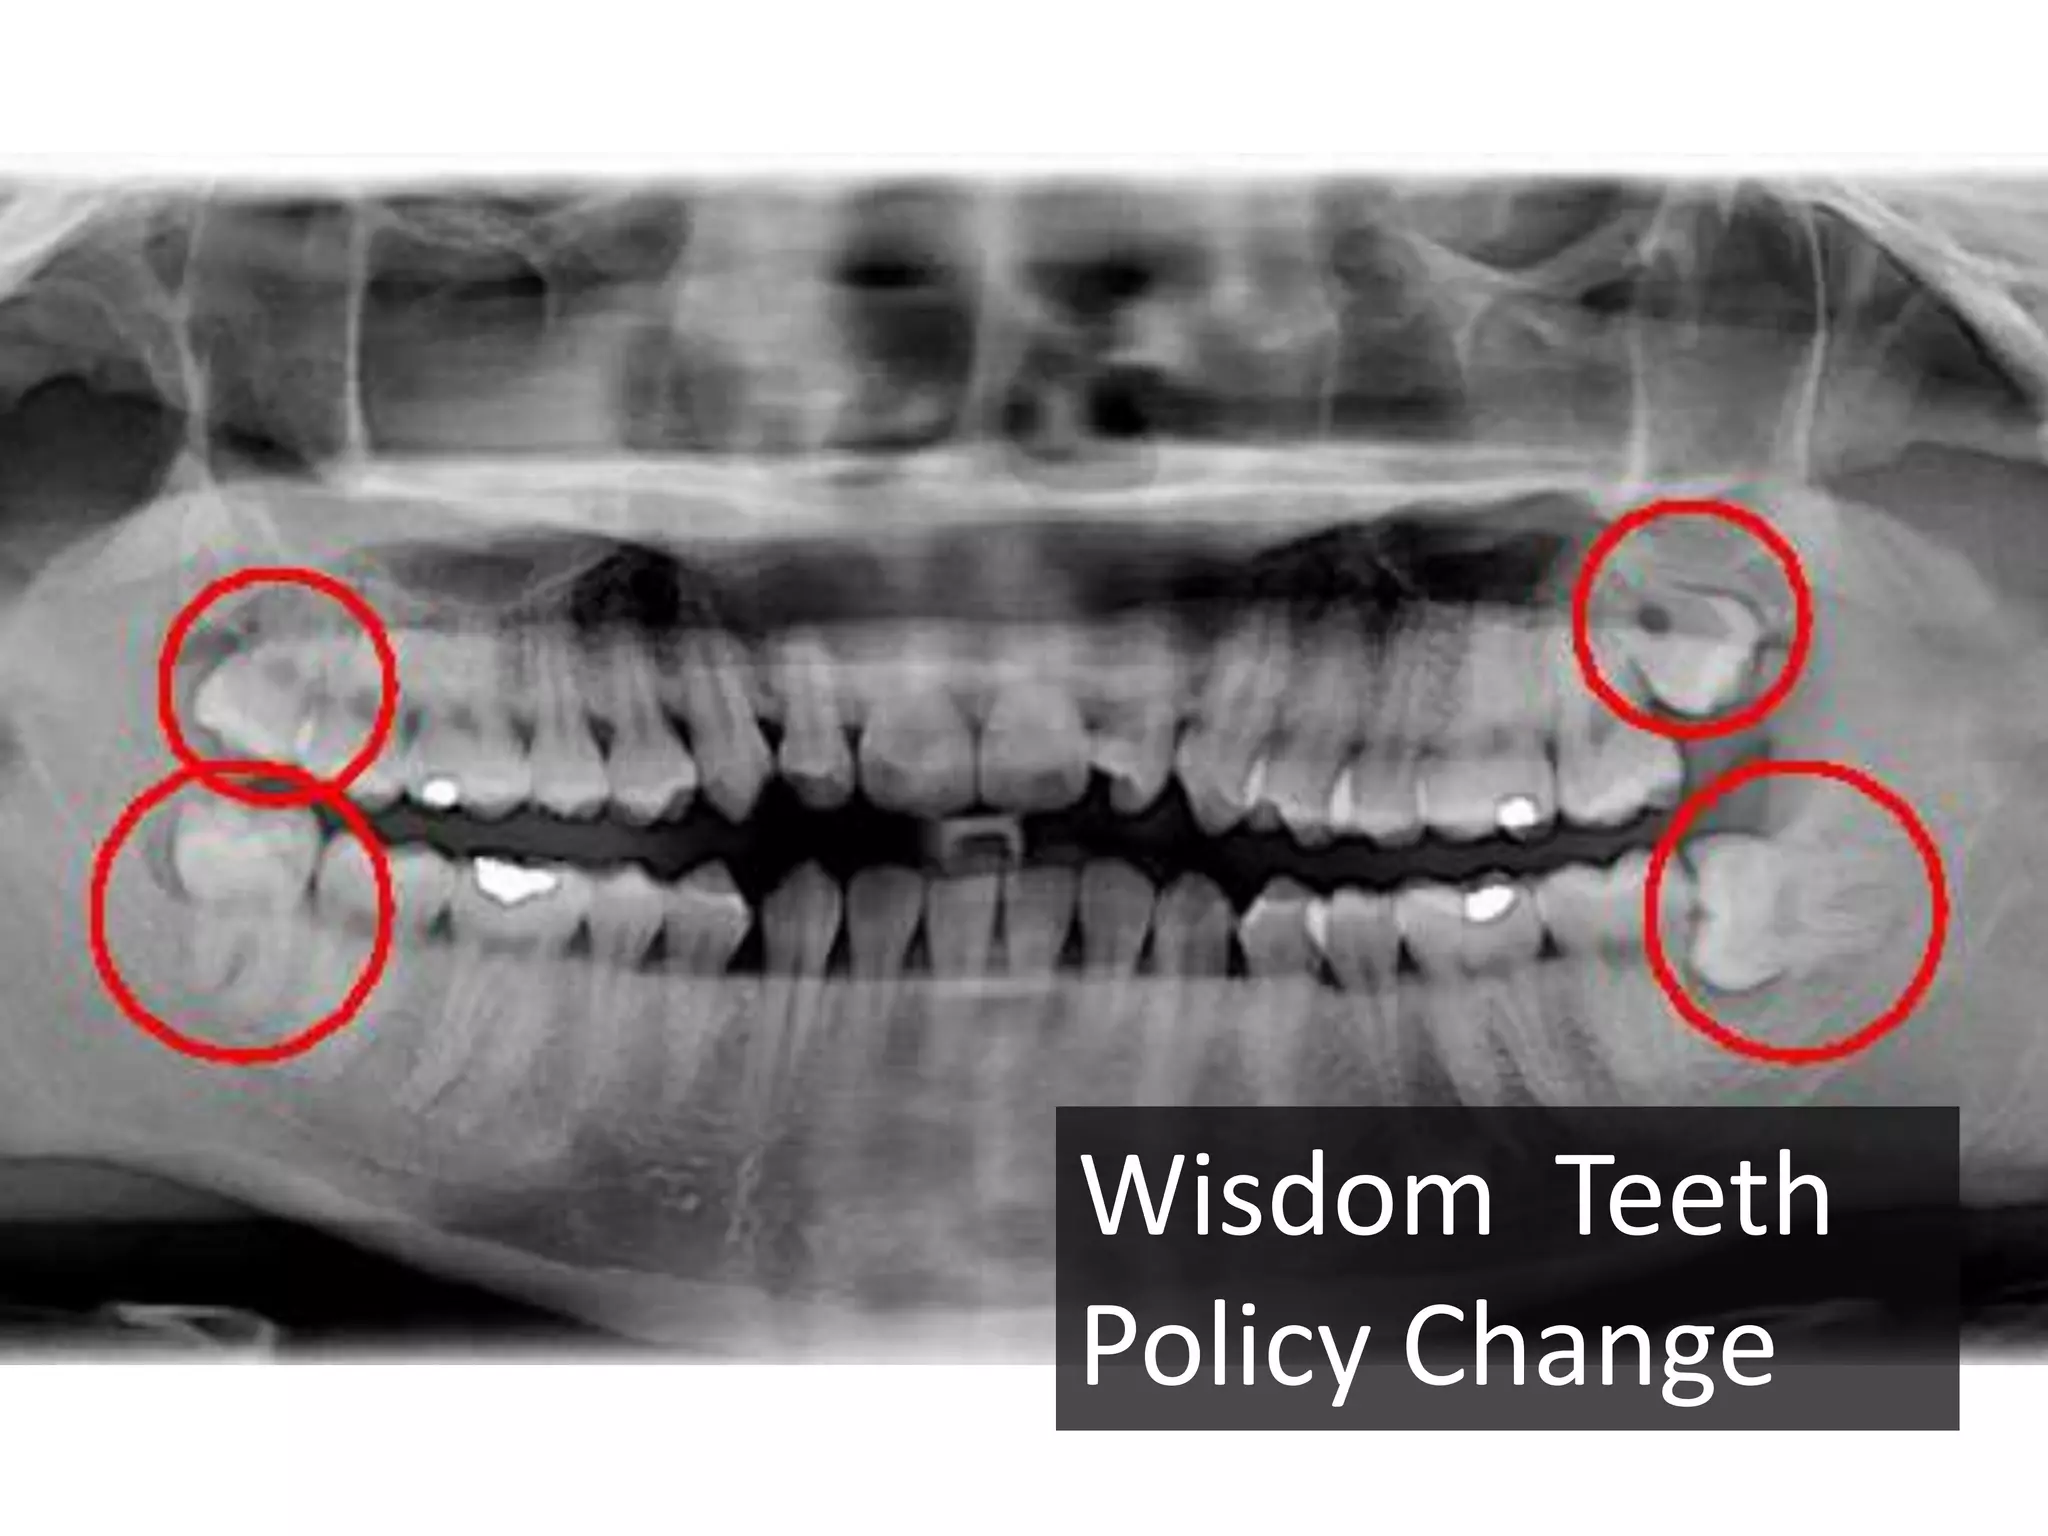

This document discusses science, software development, and the scientific method. It provides examples of cognitive biases like confirmation bias and availability bias that can impact scientific studies. Randomized controlled trials are presented as a way to reduce biases. The importance of practicing evidence-based decision making and maintaining close relationships with academia to stay informed on new research is emphasized. Disclosure of interests is also highlighted to ensure objectivity.